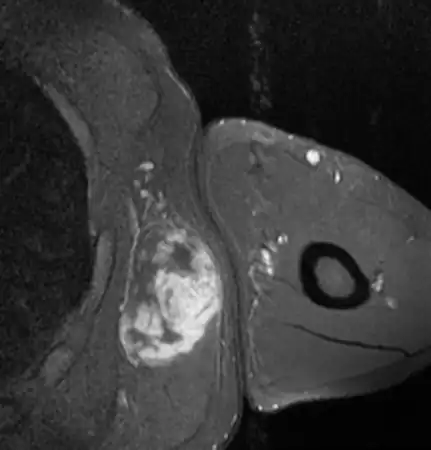

| Top: Lipoma Bottom: MRI myxoid liposarcoma of high grade in axilla | |